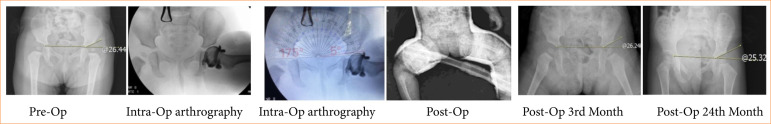

Purpose: To investigate the relationship between the cartilage acetabular index and acetabular development and secondary dysplasia.

Methods: A total of 58 hips underwent intraoperative arthrography-guided open reduction or limited open reduction due to developmental hip dysplasia between 2011 and 2015 was included in the study. We evaluated patients with acetabular angle 8º as group 2. Intraoperative acetabular cartilage index measurements were performed, and patients with low and high cartilage acetabular index were divided into two groups.

Results: There was a correlation between the cartilage acetabular index value, which indicates preoperative cartilage acetabular coverage, and acetabular development and secondary acetabular development.

Conclusion: The cartilage acetabular index is a technically easy and uncomplicated evaluation method that can be used to estimate acetabular development and should be used routinely together with the bone acetabular index.